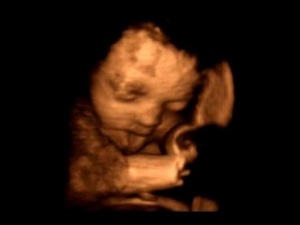

Парламент Азербайджану приступив до розгляду доопрацьованого законопроекту, що забороняє лікарям повідомляти батькам стать майбутньої дитини. Про це повідомляє Day.Az.

Новий закон "Про репродуктивне здоров`я і планування сім`ї" розроблений у зв`язку з традиційною перевагою жителів країни мати сина, а не дочку. Завдяки цьому широкого поширення набула практика селективних абортів (позбавлення від плодів жіночої статі), що веде Азербайджан до демографічної кризи.

За статистикою, протягом останніх 12 років дівчатка становлять лише третину новонароджених, тоді як нормальним співвідношенням вважається 100 дівчаток на 105 хлопчиків. Це привело до того, що в 1-6 класах шкіл на 16 учнів чоловічої статі припадає тільки 6 жіночої.

Якщо закон буде прийнятий, лікарям заборонять розголошувати батькам стать майбутньої дитини до закінчення першого триместру вагітності. У разі затвердження поточної редакції законопроекту він набуде чинності вже в 2010 році.

Автори законодавчої ініціативи розраховують, що вона допоможе скоротити число селективних абортів і виправить демографічну ситуацію в країні.